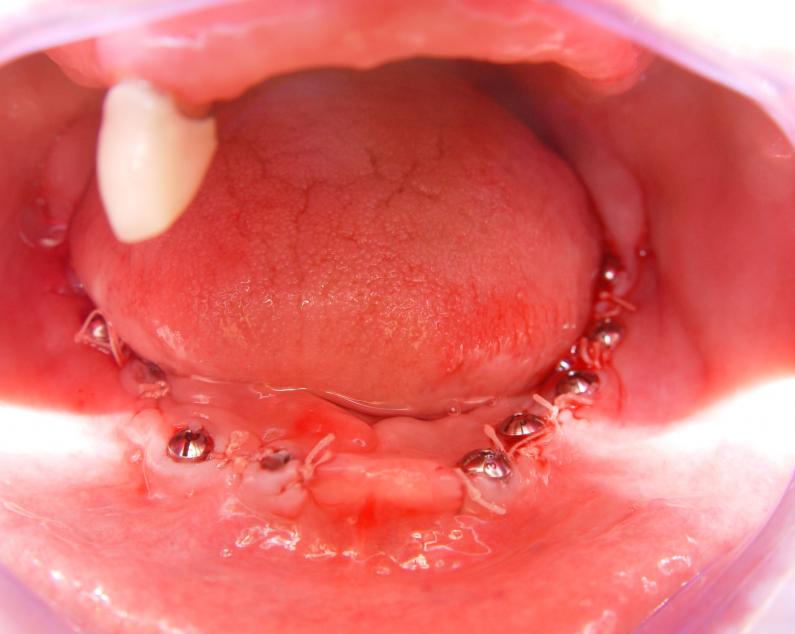

Установка 10 имплантантов на беззубую челюсть с помощью компьютерной программы: Имплантанты установлены

Имплантанты установлены